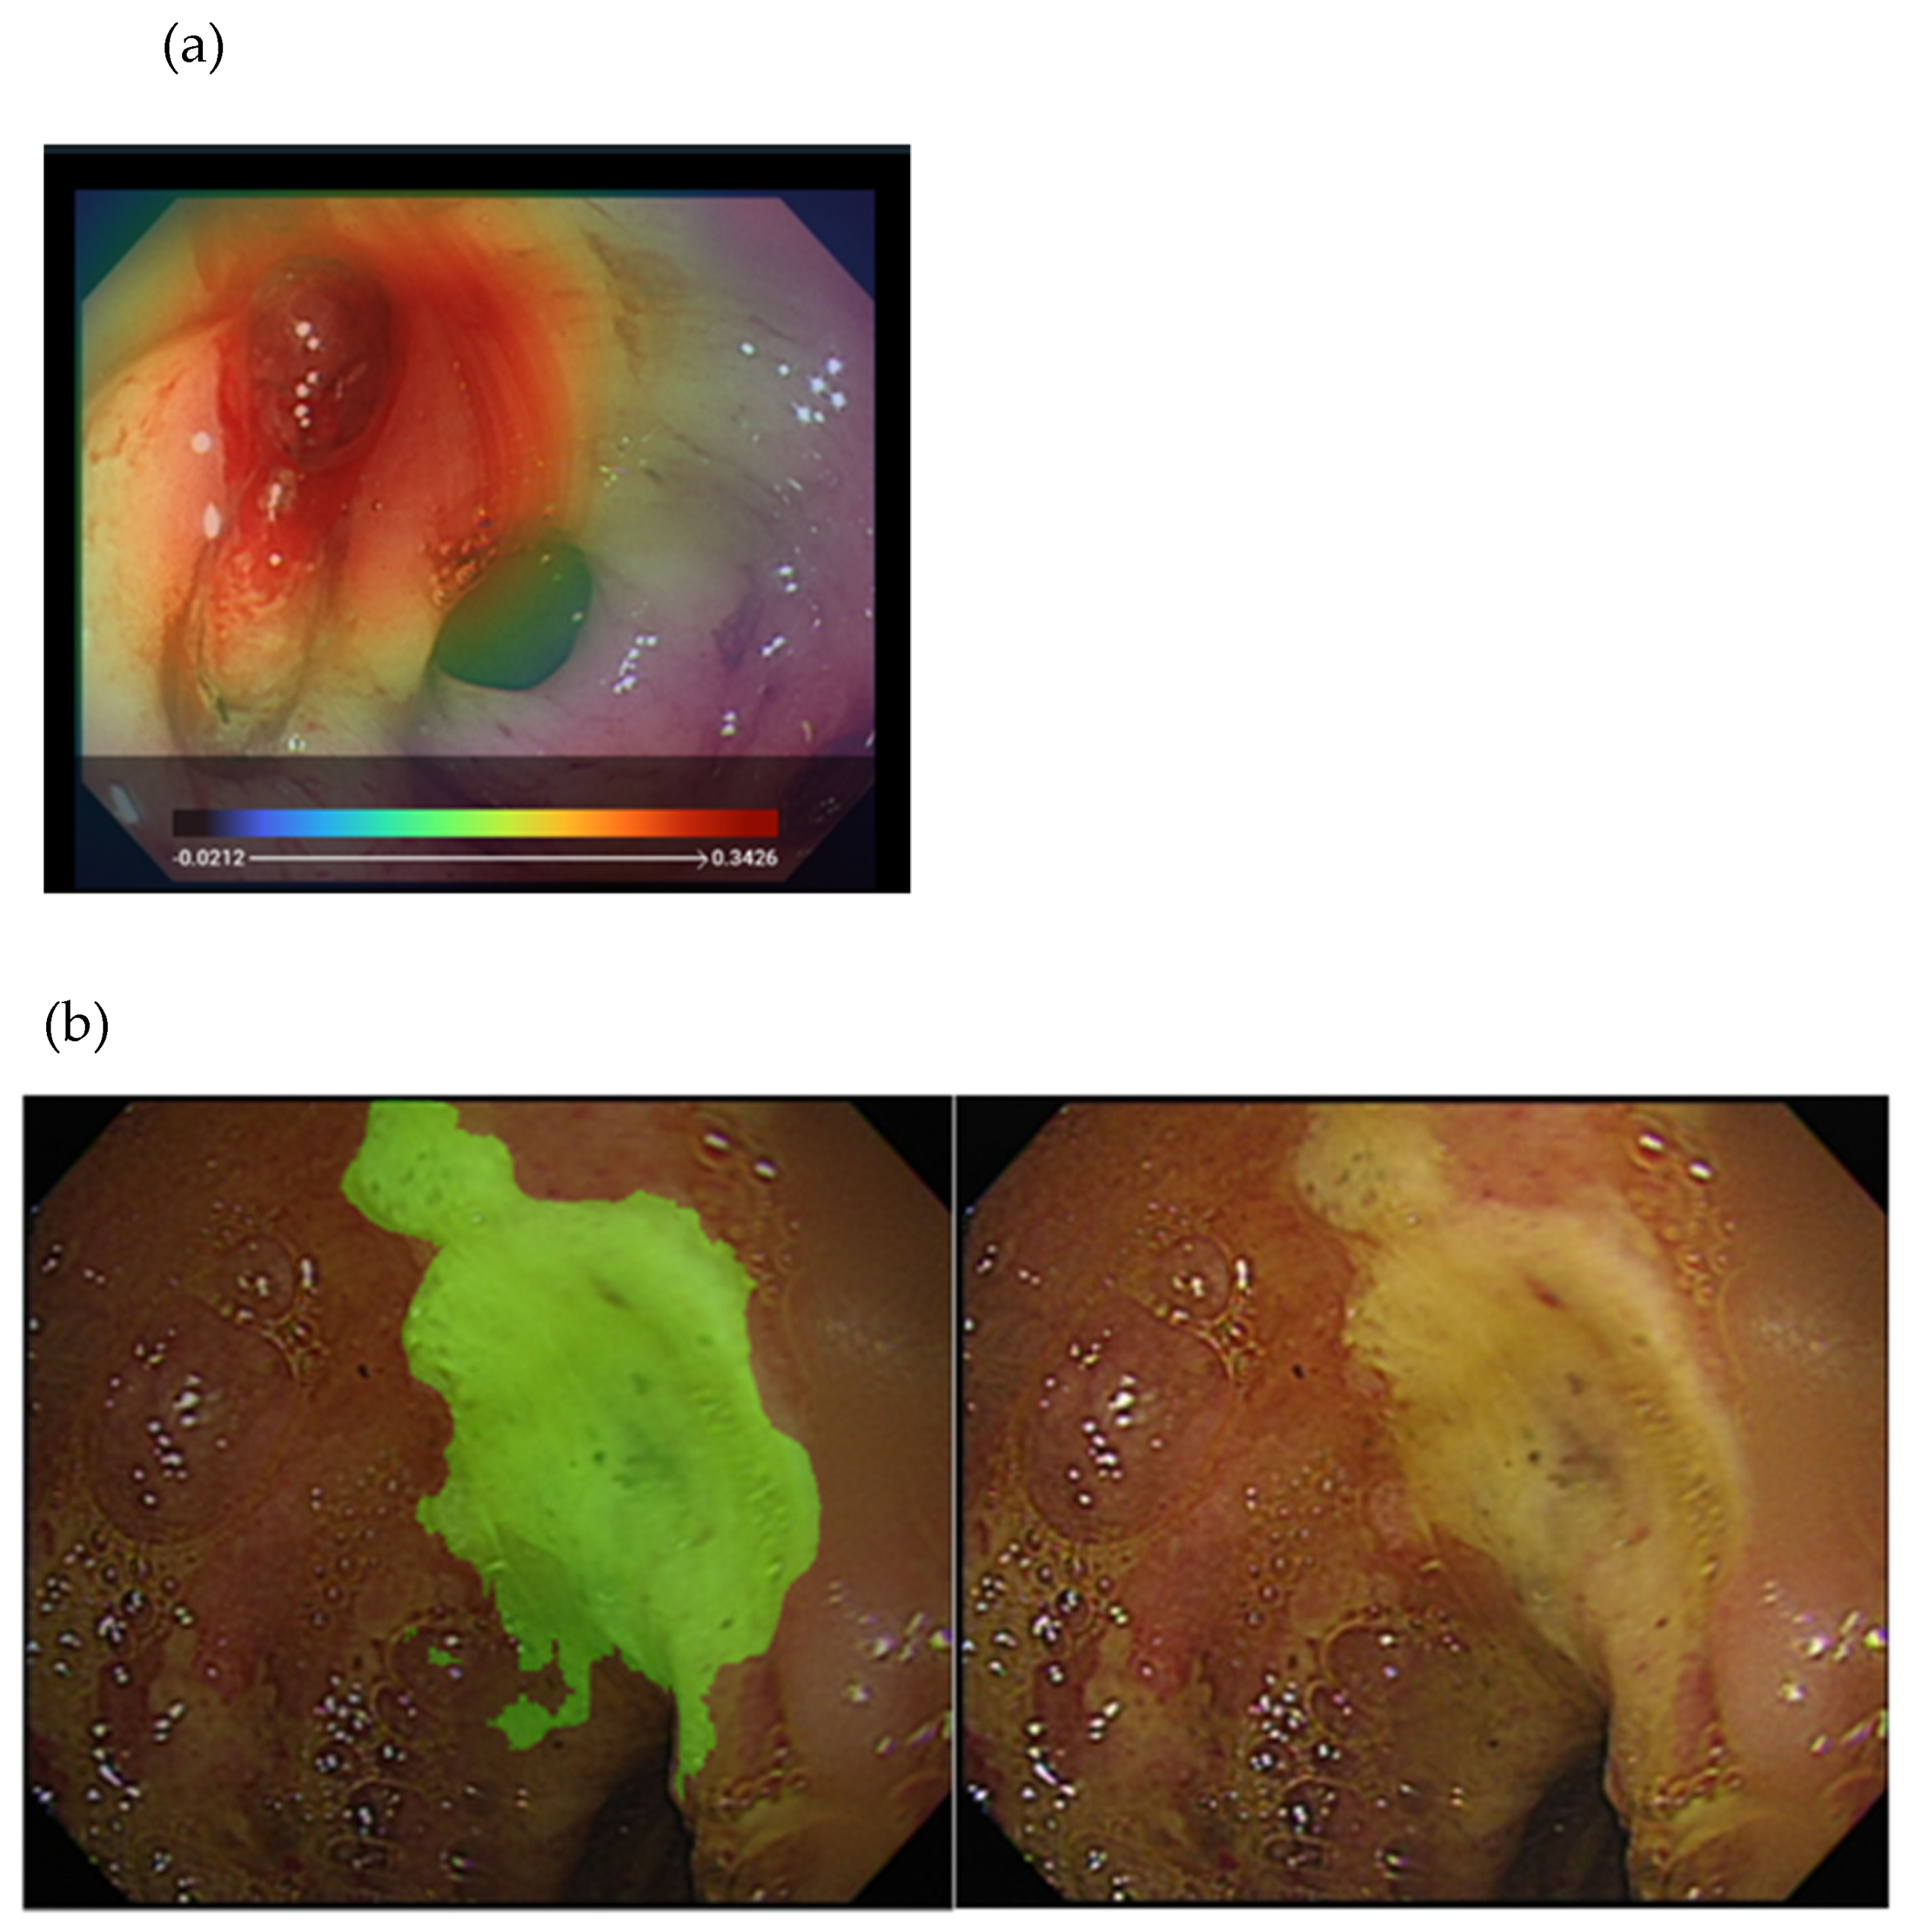

- Yen, H.-H.; Wu, P.-Y.; Su, P.-Y.; Yang, C.-W.; Chen, Y.-Y.; Chen, M.-F.; Lin, W.-C.; Tsai, C.-L.; Lin, K.-P. Performance Comparison of the Deep Learning and the Human Endoscopist for Bleeding Peptic Ulcer Disease. J. Med. Biol. Eng. 2021, 41, 504–513. [Google Scholar] [CrossRef]